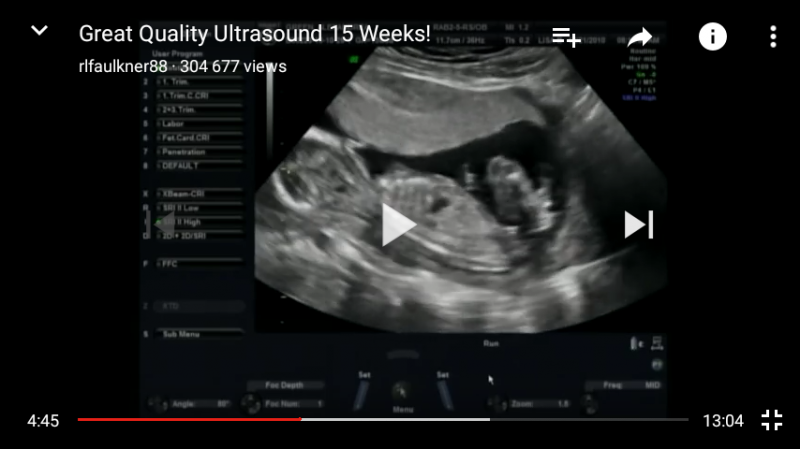

Norejau kurti nauja tema. Ja geriau butu pavadinti pagal NUB teorija.

sia teorija susidomejau gan atsitiktinai, kai vyrui pavyko pafilmuoti musu trecio …

Na pagal nub teorija ne visai taip. nes pagal sia teorija nustatuneja lb anksti, nuo 12 sav. Ten reikalingas sagitalinis vaisiaus vaizdas (vaizdas is sono, isilgai stuburo) ir esme, kad vertinamas nub organas. kuris pas berniukus issivysto i peni, pas mergaites i klitoriu. Esme sio organo uzuomazgeles kampas ir dydis.

Is nuotraukos, kurias duoda gines, laaaabai retai, kada buna pagautas reikiamas kampas. Visai kas kita, kai ziuri nufilmuota irasa. Tada, galima 80-90 proc tikslumu atspeti. O is tokios nuotraukos tik burimas, kaip su ziedu